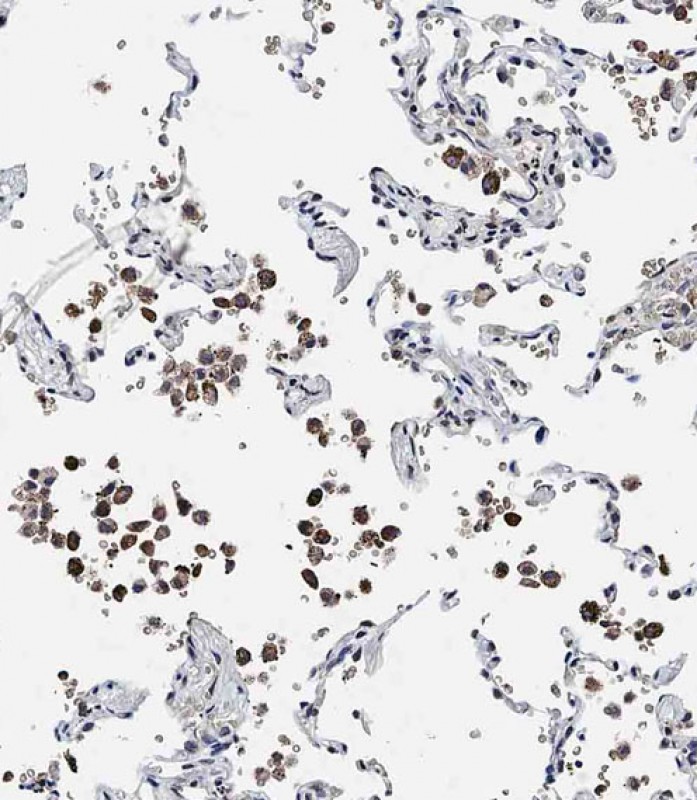

IHC 1/100 Human,Mouse,Rat

ADAMTS17 antibodies, typically polyclonal or monoclonal, are generated in hosts like rabbits or mice using immunogenic peptide sequences. They enable protein detection via techniques such as Western blotting, immunohistochemistry (IHC), or immunofluorescence (IF). These antibodies aid in studying ADAMTS17's tissue distribution (e.g., in eyes, heart, skeletal tissues), expression patterns during development, and dysregulation in diseases. Recent studies also explore its potential as a biomarker or therapeutic target. Validation includes specificity checks using knockout controls or siRNA knockdown. Researchers use these tools to unravel ADAMTS17's biological functions, interactions with ECM components like fibrillin-1. and contributions to connective tissue pathologies.